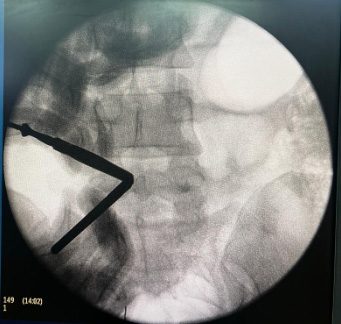

Intraoperative fluoroscopy image showing steps of triangulation at spino-laminar junction.

As orthopedic surgeons, ‘triangulation’ is a familiar word from arthroscopic training, and UBE exactly follows the same principles. It basically involves bringing the spine instruments in the working portal in view with the endoscope in the viewing portal. This step is performed under fluoroscopy guidance and could be challenging for the early adopters. It is important to be calm, focus on the process and take your time in the initial cases.

Especially in patients with high body mass index and thicker soft tissue, maintaining a proper triangulation could be arduous. Attending hands-on UBE workshops and cadaveric training can speed up the learning process.